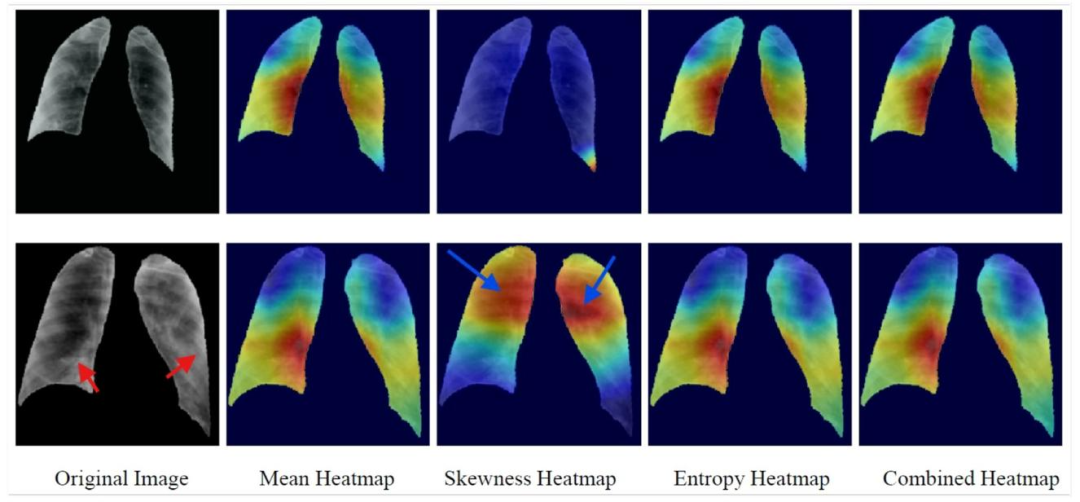

Fig. 4. SFMOV-based heatmap visualization showing a COVID-19 image detected as COVID-19 (row 1) and a COVID-19 image detection as viral pneumonia (row 2). Red arrowsindicate consolidation and blue arrows indicate healthy parenchyma (the latter is what is focused on).

图4. 基于SFMOV的热图可视化,展示了被检测为COVID-19的COVID-19图像(第1行)和被检测为病毒性肺炎的COVID-19图像(第2行)。红色箭头指示实变区域,蓝色箭头指示健康的实质组织(后者是关注的焦点)。